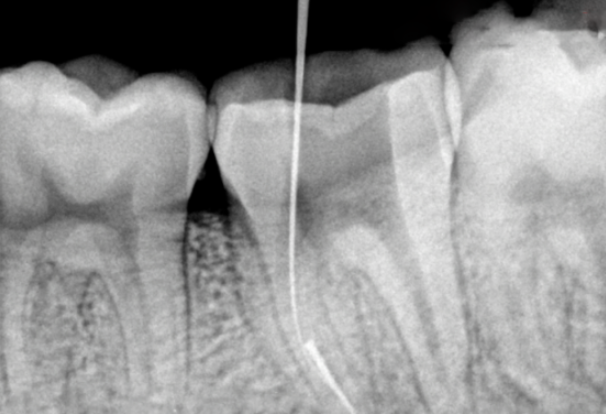

然后准备可能会使用到的器械。P钻、扩大针、钨钢小球钻、大小针头各一(小针头可以紧密的放入大针头内)、超声锉。选择合适P钻,将P钻尖端磨成平面。用钨钢小球钻在平面中央磨出一个小洞,直径比断针折断面直径略大,深1-1.5mm。

选择小针头的时候,以针头的外径大于断针折断面直径,内径小于或等于断针折断面直径为宜。然后将小针头的尖端磨平,再从平面的中央位置纵向磨开1.5-2mm,并向两侧稍稍分离。大针头也将尖端磨平。将小针头放入。至尖端磨开处时可以卡住。然后开始操作。

先在断针冠方的根管做通畅的通道。用P钻从最小号逐号进行。一直到准备好的P钻型号。根据手感慢慢的将断针端进入磨好的小洞内,去除断针端1mm左右大部分的牙本质。

再用超声锉去除断针端周围剩余牙本质。然后将超声锉放在断针的侧面震动。以求将断针震松。运气好可以直接震出断针。将小针头慢慢放入根管,顶端的分离处慢慢套入断针,稍稍卡住。再将大针头套入小针头至顶端,慢慢卡紧,最后拔出断针。